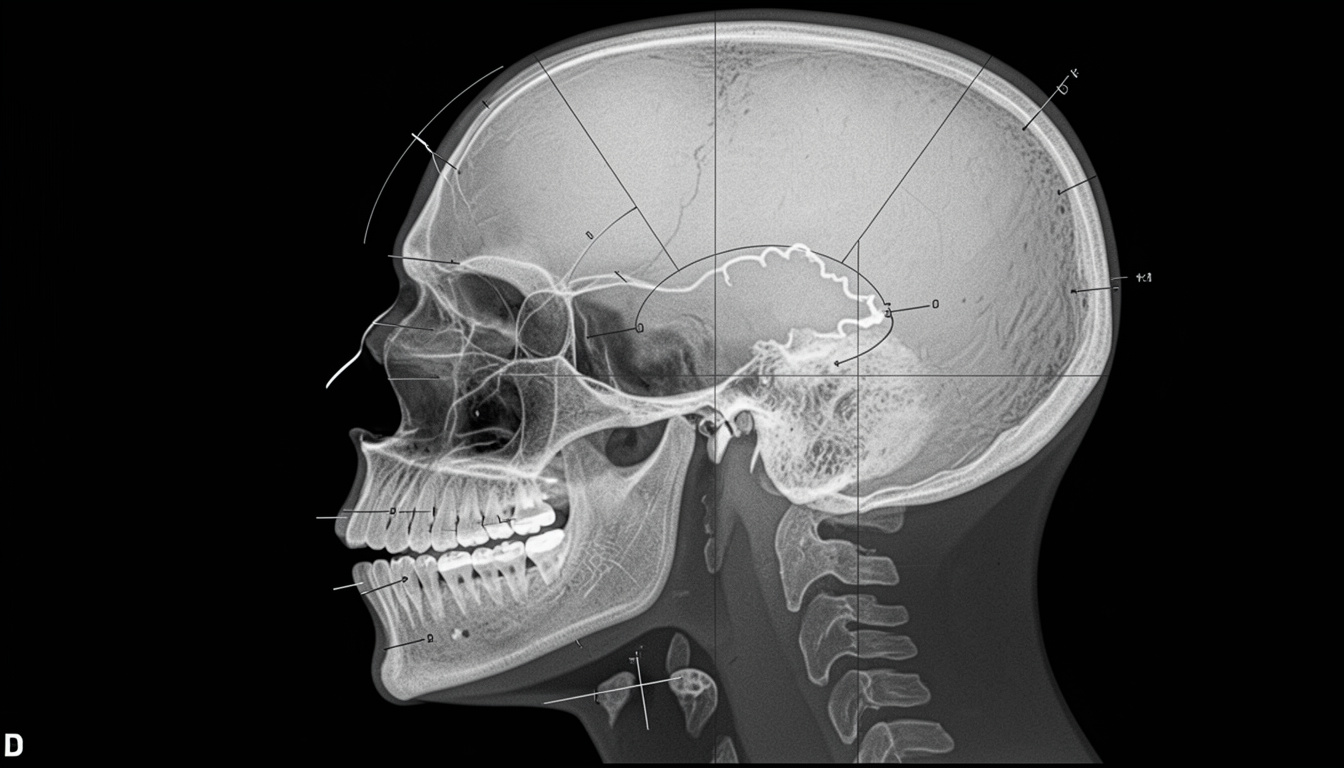

Telerradiografía y análisis cefalométrico

La radiografía lateral de cráneo con análisis cefalométrico permite medir la posición real del maxilar y la mandíbula respecto a la base craneal. Es la herramienta que permite distinguir con precisión si el origen es dental, esquelético o mixto, y orienta la planificación del tratamiento.